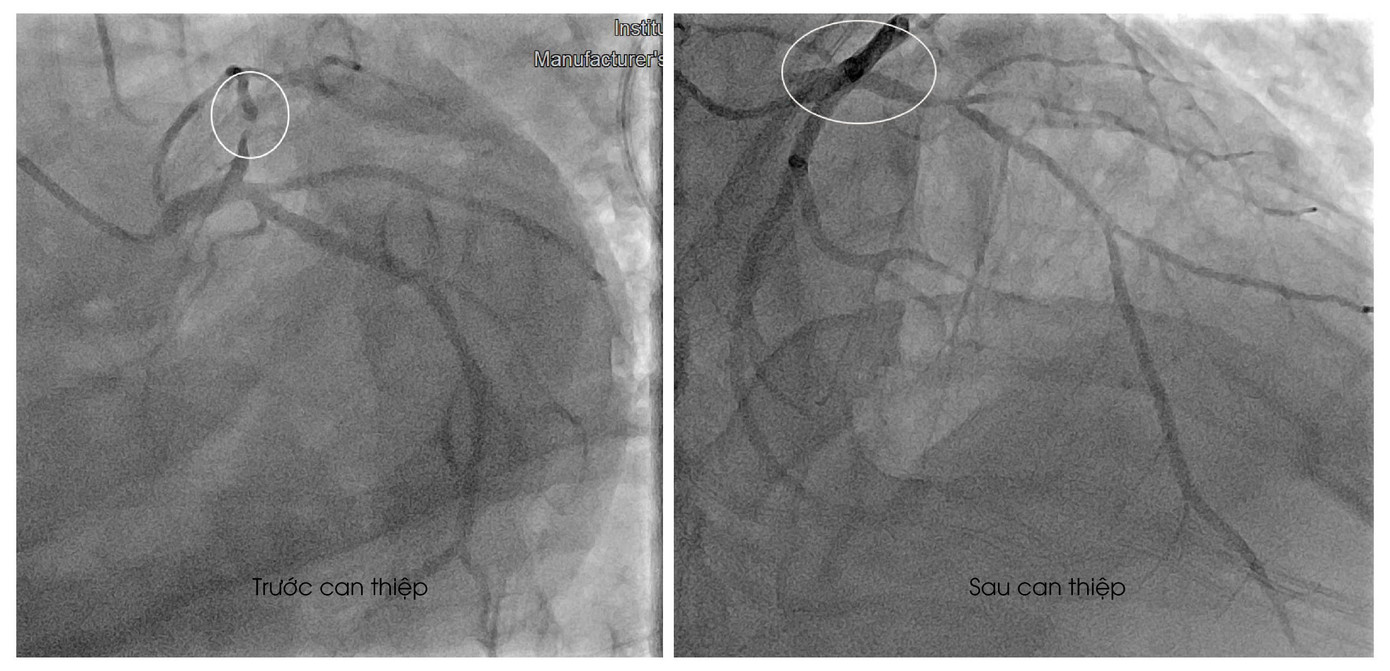

| Hình ảnh mạch máu của bệnh nhân bị tắc trước và sau can thiệp |

Thời điểm nhập cấp cứu tại Bệnh viện Đa khoa S.I.S Cần Thơ, bệnh nhân trong tình trạng lơ mơ. Qua kiểm tra, bác sĩ xác định bệnh nhân bị nhồi máu cơ tim cấp. Ngay lập tức, người bệnh được chỉ định can thiệp mạch vành. Trong quá trình can thiệp, bác sĩ ghi nhận bệnh nhân bị tắc mạch máu lớn, ê kíp bác sĩ đã đặt stent tái thông mạch máu. Một ngày sau can thiệp, bệnh nhân đã qua được nguy kịch, sức khỏe đang dần bình phục.